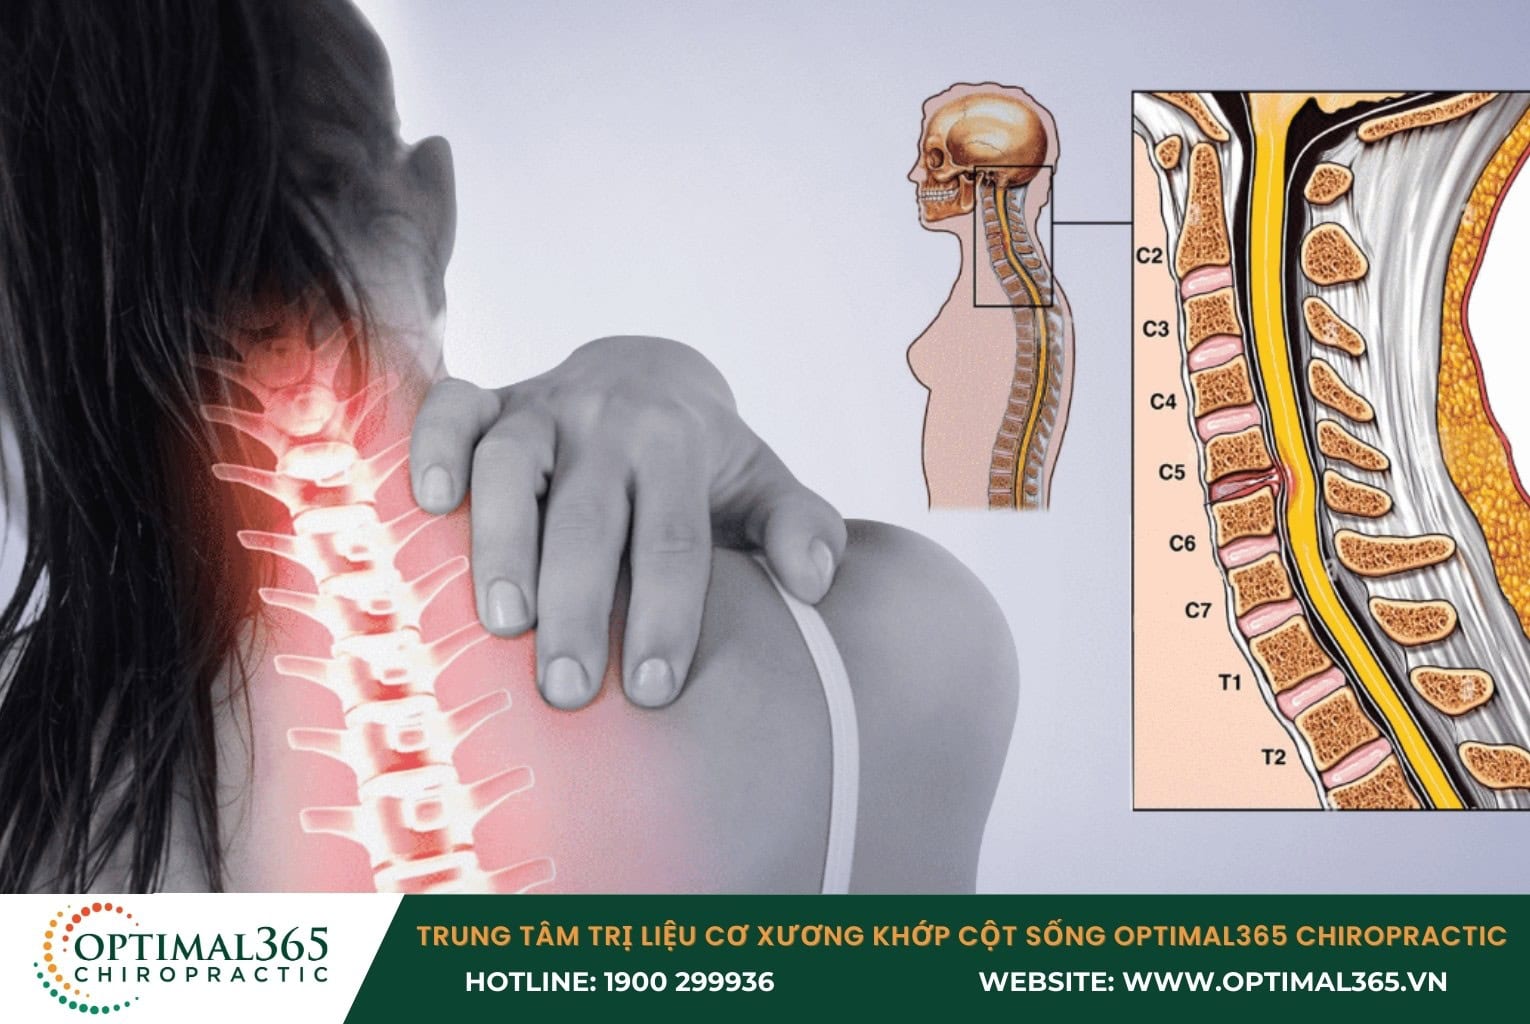

Cấu tạo đốt sống cổ, thoát vị đĩa đệm cột sống cổ là gì?

Cột sống cổ được cấu tạo bởi 7 đốt sống, bao gồm: C1, C2, C3, C4, C5, C6, C7 và liên kết với nhau bằng các đĩa đệm, hơi uốn cong theo hình chữ C . Mỗi đĩa đệm như một chiếc “đệm cao su”, có chứa nhân nhầy ở giữa và bao xơ ở ngoài, giúp giảm chấn động và tạo điều kiện linh hoạt cho cột sống.

Trong đĩa đệm bao gồm nhân nhầy nằm bên trong (có kết cấu như lớp gel) chứa thành phần proteoglycans, bao xơ hình tròn bên ngoài với cấu tạo chính là các sợi collagen. Cuối cùng là tấm sụn nằm giữa mân sụn vùng thân sống, giúp bảo vệ bề mặt thân đốt sống, tránh nhân nhầy bị ép vào.

Thoát vị đĩa đệm cột sống cổ xảy ra khi đĩa đệm bị lão hóa, rách nứt hoặc do chấn thương. Lúc này, phần nhân nhầy thoát ra khỏi bao xơ, chèn ép rễ thần kinh hoặc tủy sống, dẫn đến đau nhức và nhiều triệu chứng khác.